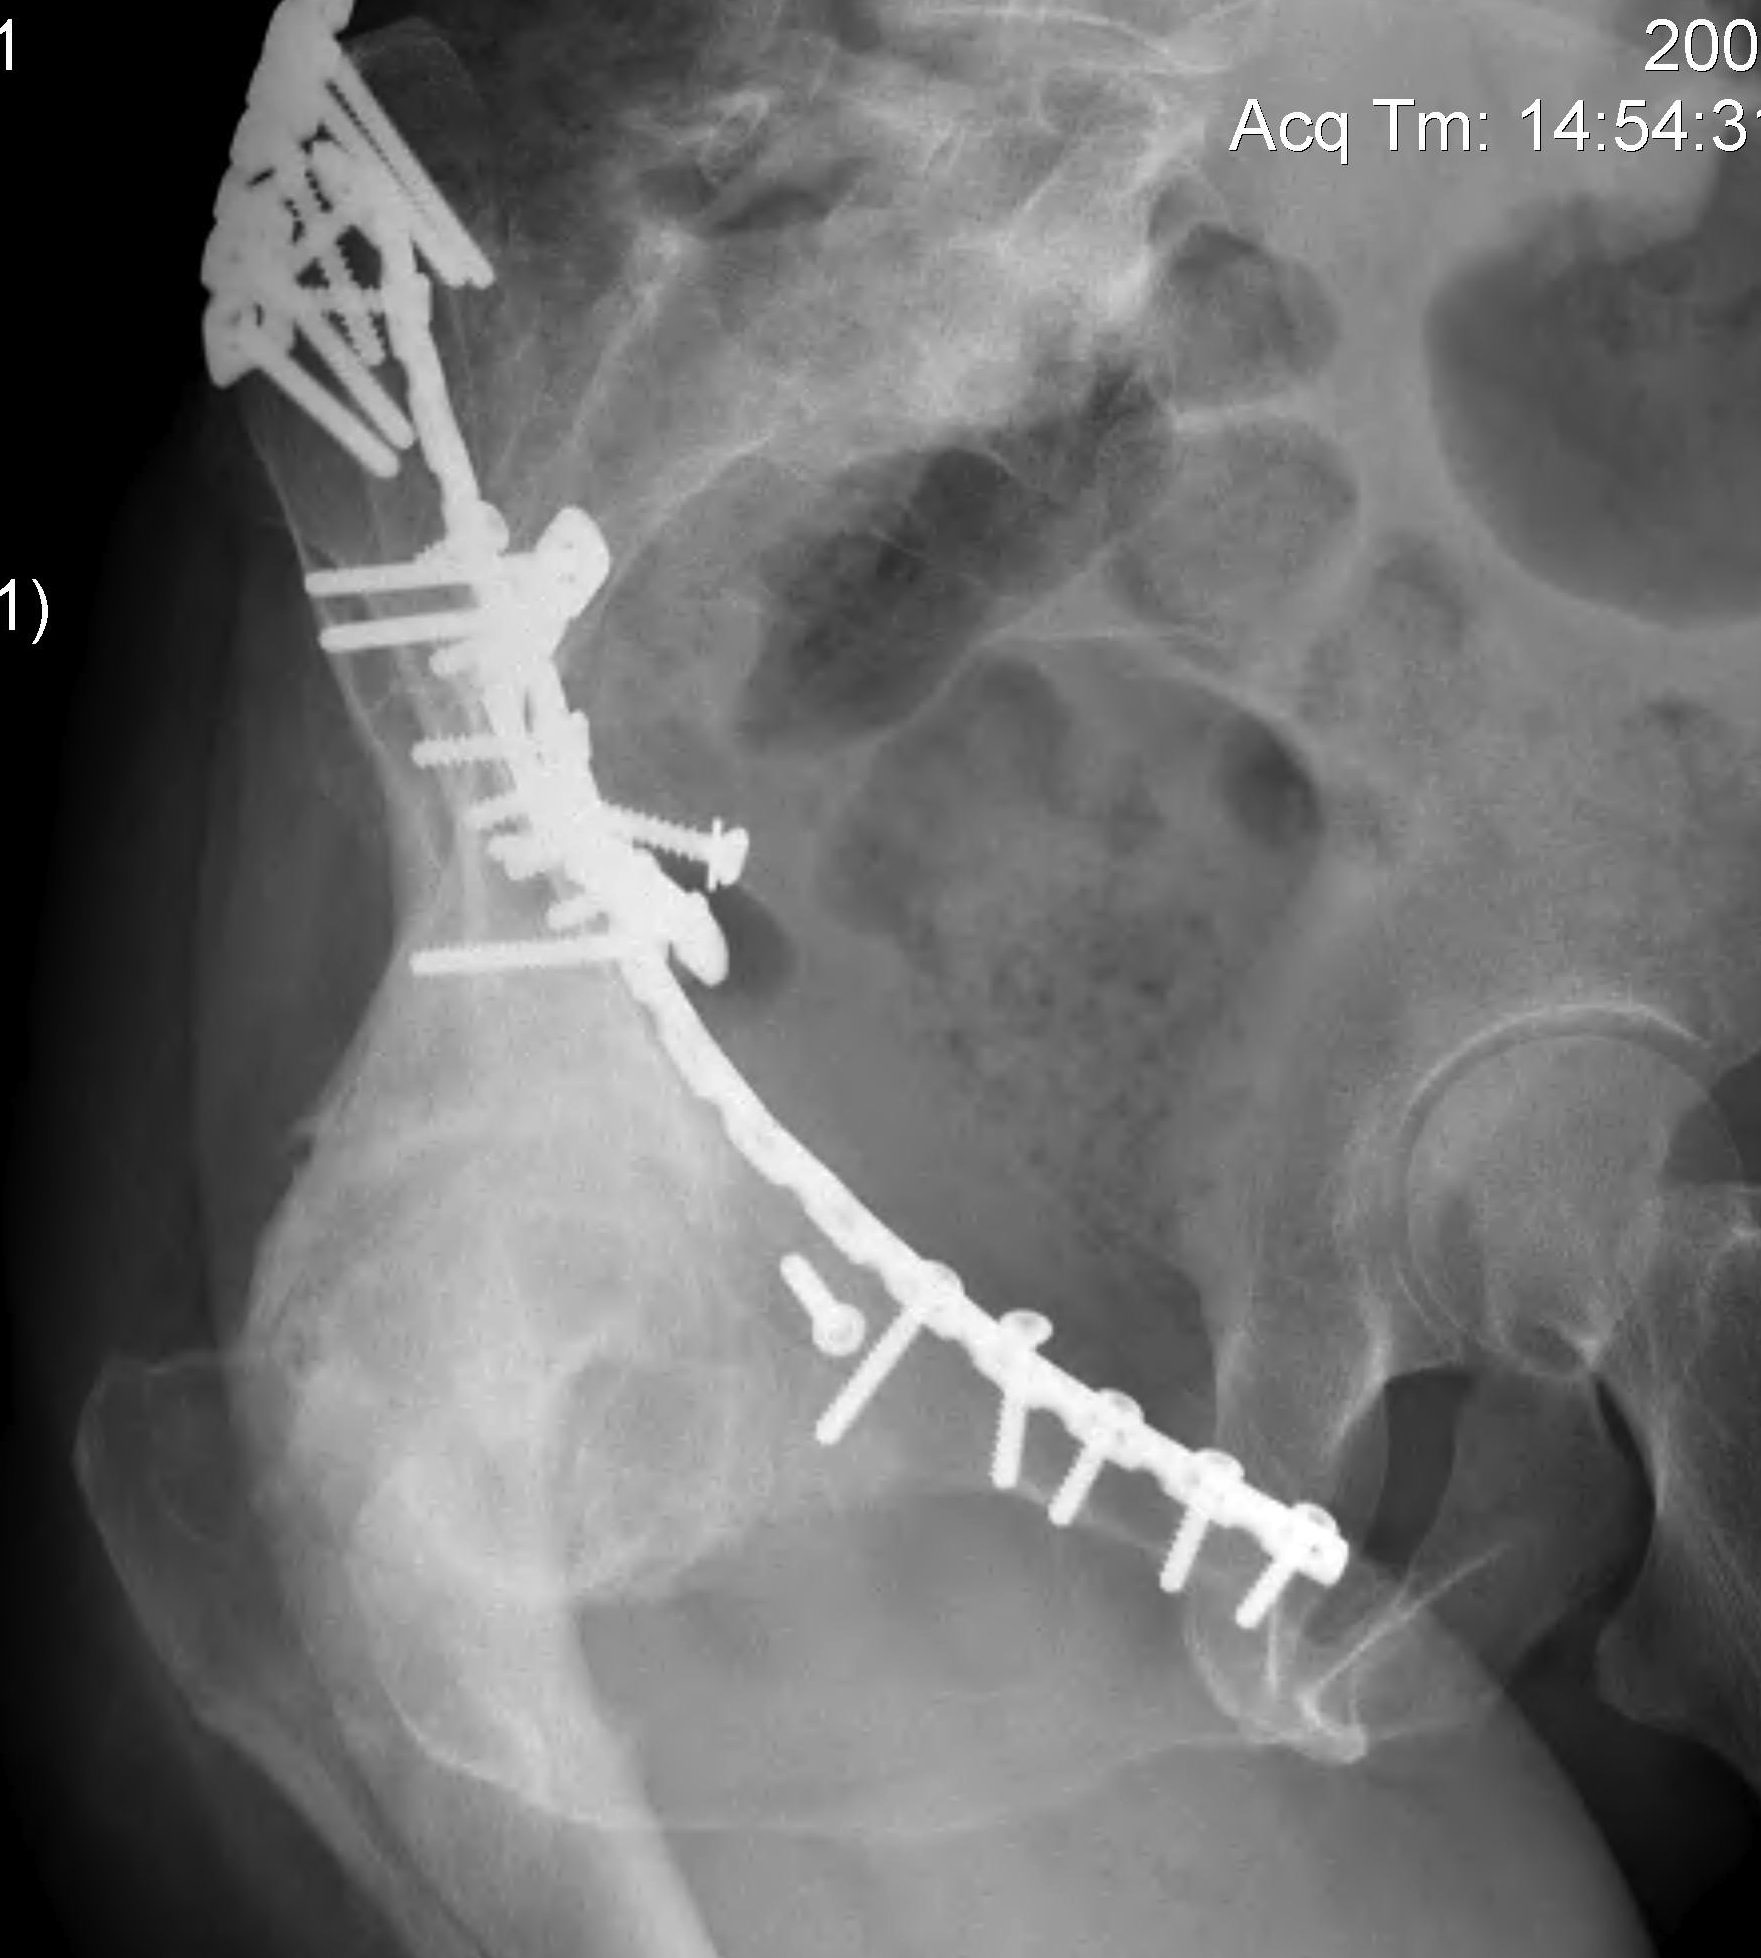

ORIF

Aim

1. Anatomic reduction

2. Provisional fixation with lag screws

3. Buttressing with curved reconstruction plates

Options

1. Posterior / Kocher-Langenbeck approach

- posterior column / wall

2. Ilioinguinal approach

- anterior column / wall

3. Extended iliofemoral approach

- Smith-Petersen extended over iliac crest

- for transverse / both column fractures

4. Triradiate approach

- Kocher-Langenbeck with anterior extension from GT to ASIS

- wide exposure for both column fractures

- high incidence HO

Preferred option is to perform

- ilioinguinal for anterior column / wall

- posterior / Kocher Langenbeck for posterior column / wall

- do both 1 week apart for combined fractures